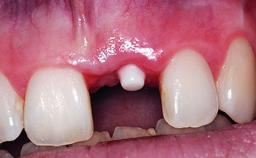

Replacement of a Compromised Upper Right Central Incisor: Hard- and Soft-tissue Augmentation, Late Placement of an RC Bone Level Implant

A 36-year-old male patient with a compromised maxillary central incisor was referred by his general dentist for consultation. The patient’s chief complaints were the gradual debonding of a temporary crown on the right central incisor and unsatisfactory esthetics due to an increasing diastema between the right central and lateral incisors. The patient reported a traumatic event some years previously, when a crown had been placed after root-canal treatment. The referring dentist wanted to provide a new crown restoration, but was concerned about the condition of the residual root. Anamnesis was negative for any other dental or periodontal pathology in the remaining dentition. The patient reported taking no medications: He was a smoker (10 to 15 cigs/day) and had realistic esthetic expectations.

Soft Tissue Anatomy Intact Defective

Soft Tissue Contour and Volume Slightly compromised